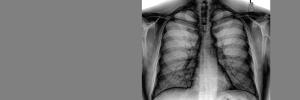

Middelweerstandige tuberkulose (MDR-TB) is 'n vorm van TB wat weerstand bied teen ten minste twee van die sterkste antibiotikas wat gebruik word om TB te behandel, naamlik isoniasied en rifampisien. Wanneer dit vergelyk word met middelvatbare TB, neem die behandeling van MDR-TB veel langer (2 jaar in vergelyking met 6 maande), is dit minder effektief (net omtrent 50% van pasiënte word genees) en meer toksies (ernstige newe-effekte sluit permanente gehoorverlies in), en die koste kan soveel as 1,000 keer duurder beloop. Sonder doeltreffende terapie kan mense met MDR-TB ander mense infekteer wat nog nooit voorheen TB gehad het nie.

Die Demokratiese Republiek van die Kongo (DRK) het 'n bevolking van 'n beraamde 81 miljoen mense en dra 'n hoë lading van TB, TB/MIV en MDR-TB. Volgens die Wêreld Gesondheidsorganisasie (WGO), was daar 'n beraamde 262,000 van nuwe gevalle van TB en 56,500 TB-verwante sterftes in die DRK in 2017. Die tweede Kongolese oorlog het begin in 1997 en het geweldige ontwrigting veroorsaak in die gesondheidsdienste in die oostelike DRK, wat gelei het tot 'n toename in TB gevalle en TB-verwante sterftes in die gebied. In 2011, ten spyte van voortgesette siviele konflik en aktiwiteit onder militias, is die Xpert MTB/RIF assay (Xpert), 'n vinnige molekulêre diagnostiese toets vir TB wat toetsing vir rifampisien-vatbaarheid insluit (dit speur rifampisien-weerstandige TB op, of RR-TB, 'n aanduider van MDR-TB) in gebruik geneem in die Suid-Kivu provinsie van die oostelike DRK. Die uitrol van hierdie nuwe TB toets is moontlik gemaak deur die samewerking van die DRK Nasionale TB Program en die Stop TB Partnership TB se REACH inisiatief, wat befonds is deur Global Affairs Canada.

In Clinical Infectious Diseases, een van die top joernale in die veld van aansteeklike siektes berig die volgende mense/organisasies oor 'n nuwe kohort-studie waarin 16,448 pasiënte geëvalueer is vir TB tussen 2012 en 2017 in post-konflik DRK: André N.H. Bulabula, MD, MSc, PhD student, van die Departement van Globale Gesondheid, Afdeling Gesondheidstelsels en Openbare Gesondheid, Suid-Afrika en die Infection Control Africa Network, saam met kollegas van die DRK Nasionale TB Program, South Kivu Provincial Anti-Leprosy and TB Coordination, en mede-skrywers. Die navorsers het rifampisien-weerstandigheid gevind in 170 van die 1,535 pasiënte (11%) wat positief getoets het vir TB. Byna 47% van die RR-TB pasiënte is nooit voorheen gediagnoseer of behandel vir TB nie, wat suggereer dat baie van hulle geïnfekteer is deur middel van direkte kontak met pasiënte met RR-TB in hulle gemeenskappe. Genesing is bewerkstellig in 30/36 pasiënte (83%) met RR-TB wat behandel is met 'n nuwe 9-maande behandelingsregimen in vergelyking met die 84/114 pasiënte (74%) wat met die konvensionele 20- en 24-maande regimens behandel is. Faktore wat met suksesvolle behandeling geassossieer word het die volgende ingesluit: 'n gebrek aan ernstige newe-effekte van die medikasie, die verskaffing van sosio-ekonomiese aansporings, en die gebruik van tuis-gebaseerde direk-waargenome terapie deur opgeleide gesondheidswerkers uit die gemeenskap en familielede.